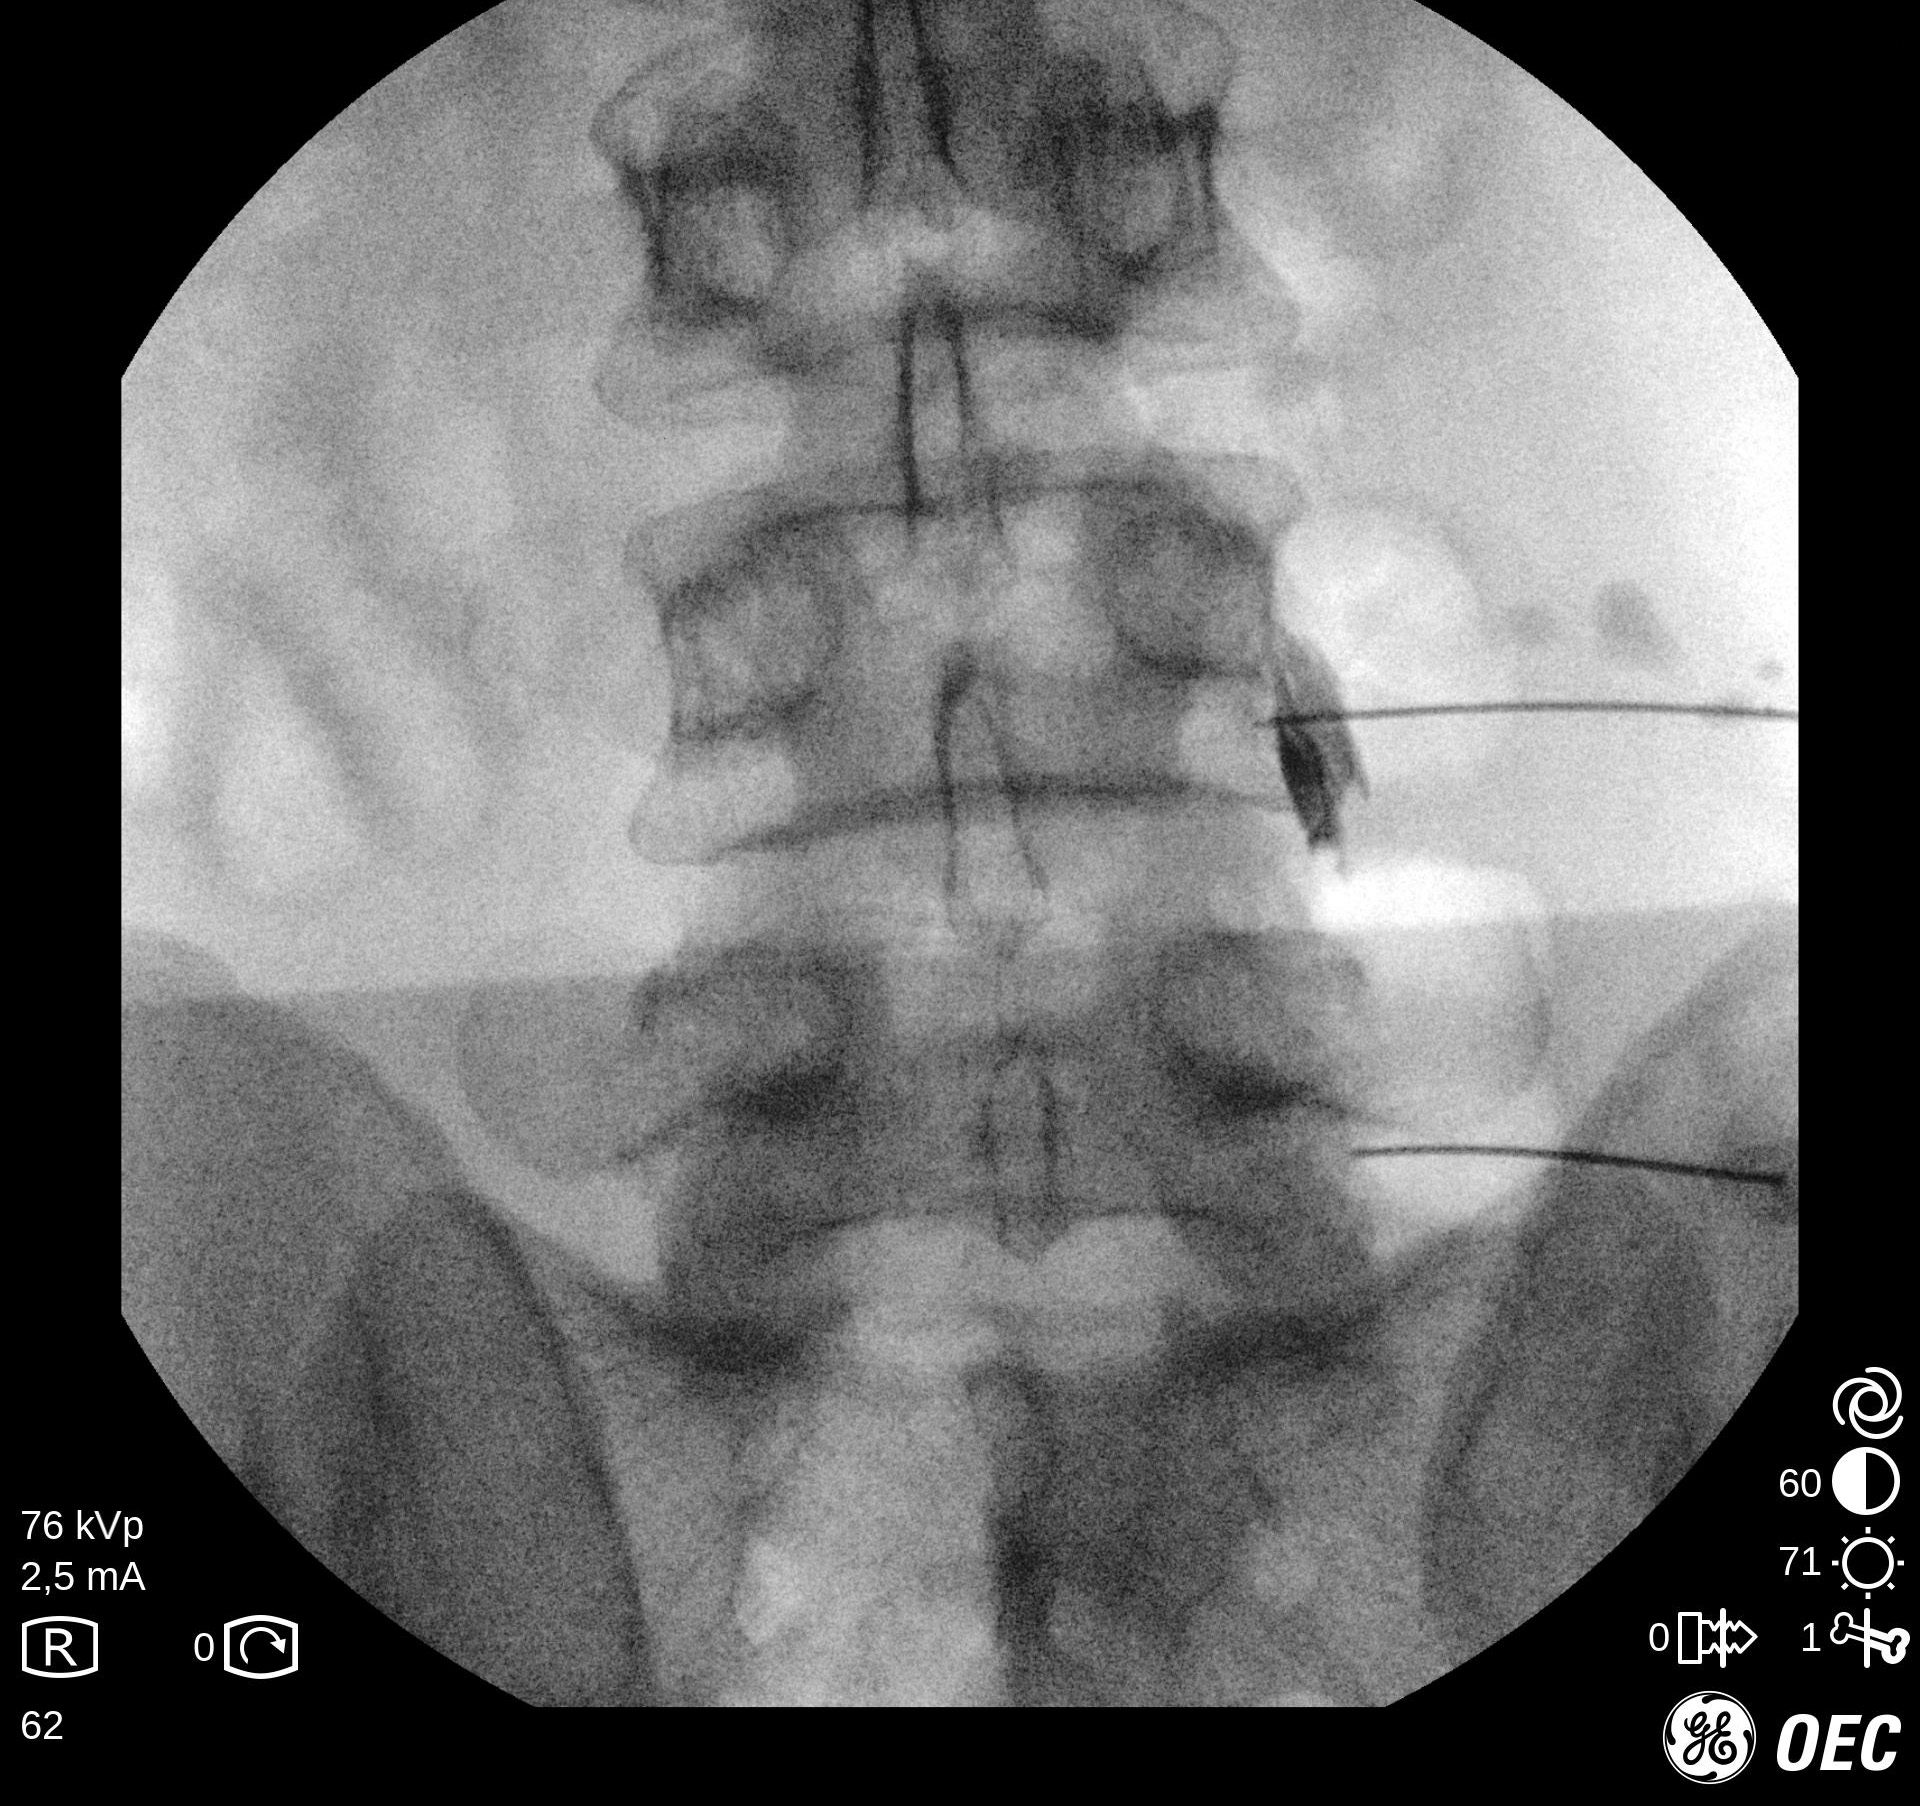

Ασθενής με 2 πολύ μεγάλες δισκοκήλες

Ασθενής 75 ετών με αδυναμία βάδισης λόγω έντονης οσφυαλγίας από έτους. Η αιτία είναι δύο μεγάλες δισκοκήλες που πιέζουν τις εξερχόμενες ρίζες των νεύρων. Με τοπική αναισθησία τοποθετήθηκαν 2 βελόνες στα στα  επίπεδα Ο4-05 και Ο5-Ι1 και έγινε  εισαγωγή μείγματος αναλγητικών. Άμεση ανακούφιση με αποτέλεσμα που διατηρείται 1 χρονο μετά.